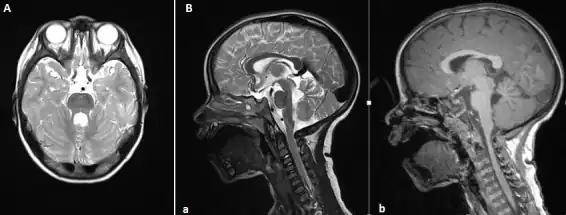

The disorder is characterized by the absence or underdevelopment of the cerebellar vermis and a malformed brain stem (molar tooth sign), both of which can be visualized on a transverse view of the head MRI scan.[19] Together with this sign, the diagnosis is based on the physical symptoms and genetic testing for mutations. If the gene mutations have been identified in a family member, prenatal or carrier diagnosis can be pursued.[6]